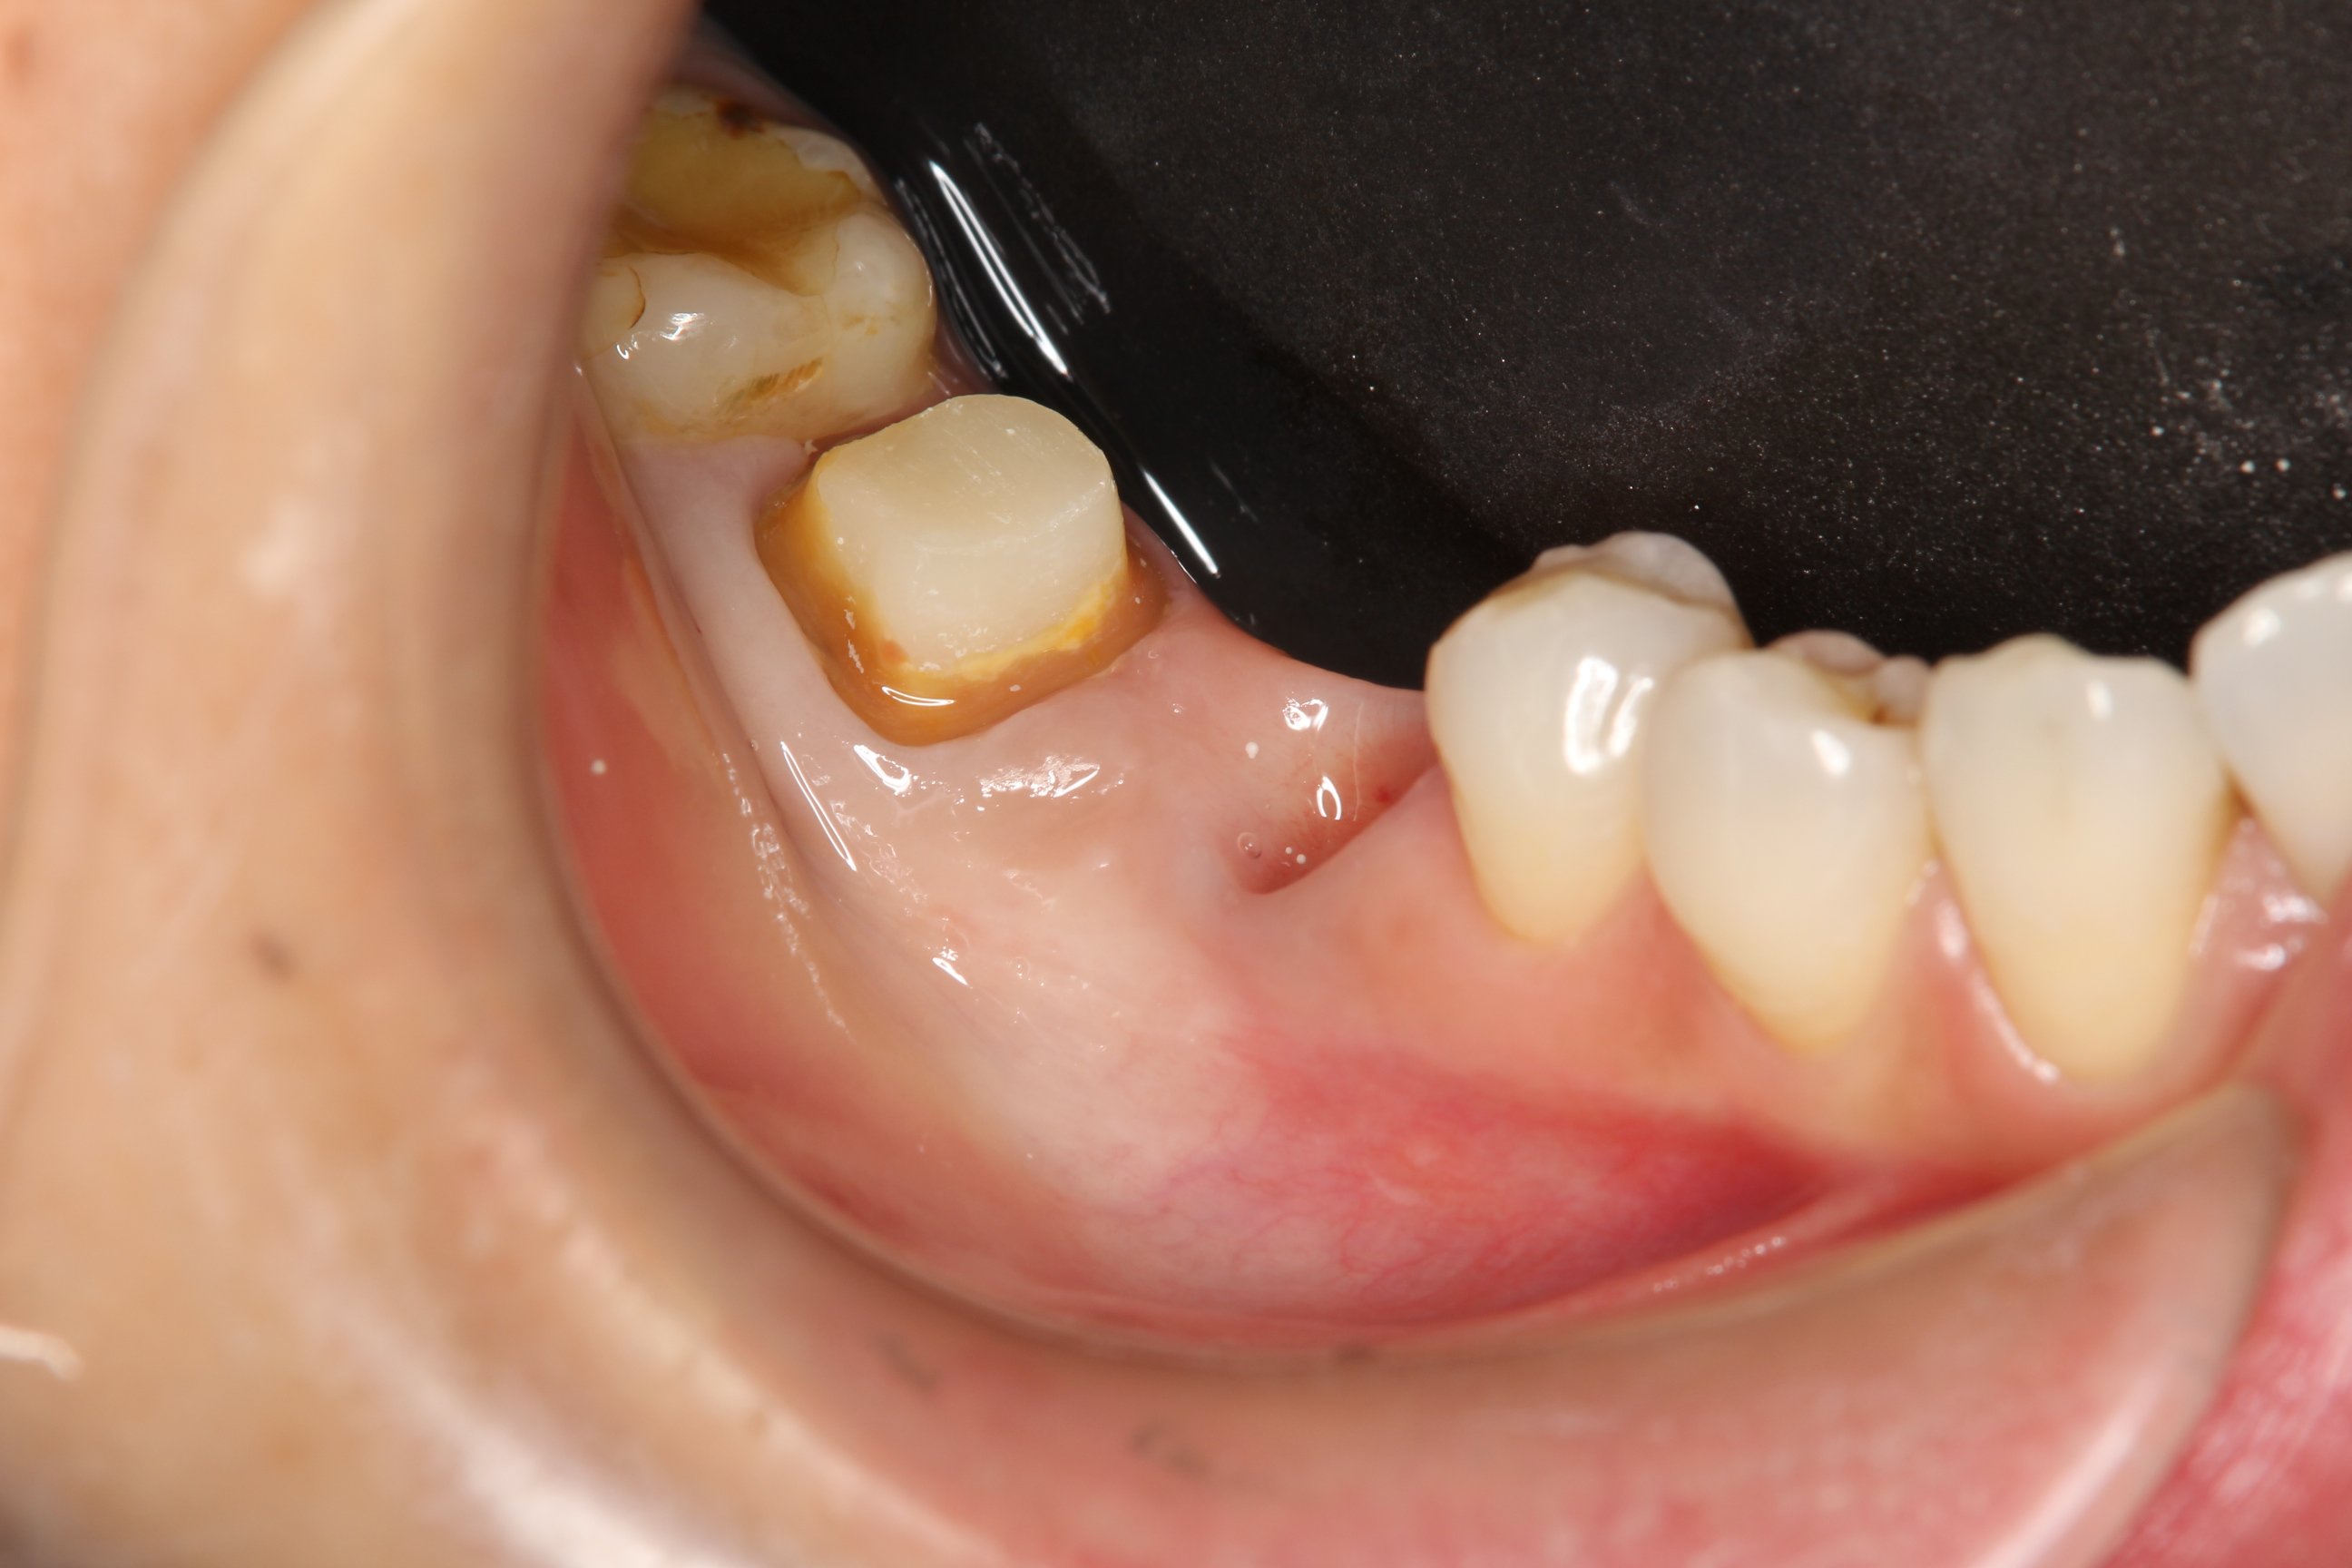

下の写真は、インプラントと天然歯にクラウンを装着する前のものです。

以前にホワイトニングも行っているので、周囲の歯の色は白く明るくなっています。